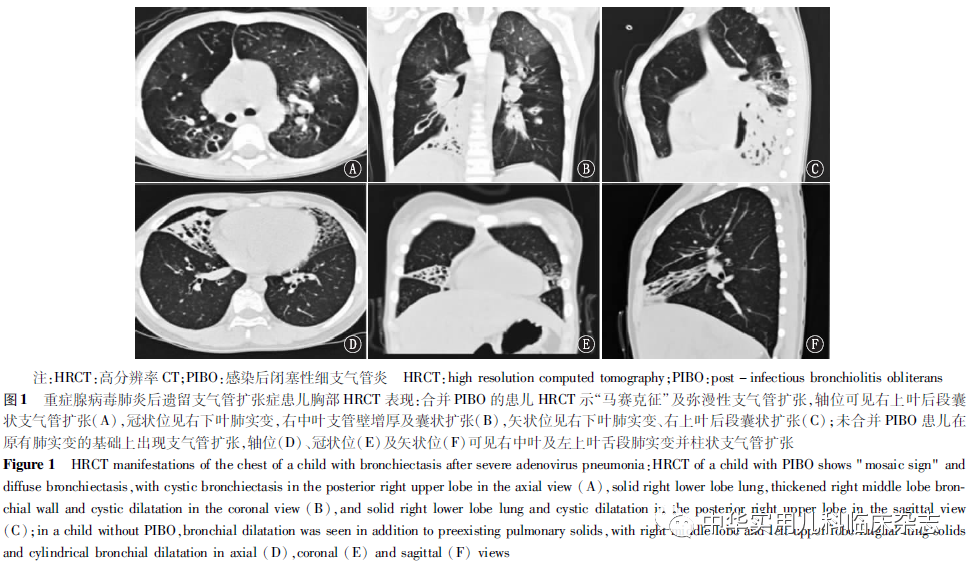

结果2.1 临床特征 2016年5月至2021年5月共收治481例重症腺病毒肺炎患儿,符合入组条件26例(26/481,5.41%),其中男18例,女8例。所有患儿既往体健,且腺病毒肺炎急性期均确诊为重症,急性期均存在发热、咳嗽、呼吸急促、三凹征(+)。26例患儿重症腺病毒肺炎发病中位数年龄为23.0(15.0,48.0)个月。确诊支气管扩张症时中位数年龄为29.5(21.0,56.8)个月,距腺病毒肺炎急性期的中位数时间为6.0(3.3,13.0)个月。20例合并PIBO,其中3例诊断PIBO时已存在支气管扩张,17例是在遗留PIBO的基础上出现支气管扩张,确诊PIBO时距腺病毒肺炎急性期中位数时间为2.0(1.5,2.8)个月,而确诊支气管扩张时距PIBO的中位数时间为5.0(4.3,10.5)个月。6例单纯遗留支气管扩张症,确诊时距腺病毒肺炎急性期中位数时间为2.0(1.0,7.0)个月。2.2 影像学检查 腺病毒肺炎急性期住院期间,26例患儿均行胸部高分辨率CT(high resolution CT,HRCT)检查,表现为多肺叶肺实变伴/不伴胸腔积液。26例患儿均在随访过程中复查HRCT发现支气管扩张(图1),20例患儿HRCT同时存在“马赛克征”,即PIBO,其中8例患儿存在不同程度的肺实变,5例患儿存在纤维条索影,3例患儿存在胸膜增厚,2例患儿存在肺囊泡。其中20例合并PIBO的支气管扩张患儿急性期肺实变累及范围均≥2个肺叶(20/20,100%)。24例(92.30%)为弥漫性支气管扩张(即>2个肺叶),HRCT显示支气管扩张最常累及左下叶、右下叶(各21例,80.77%),其次为右上叶(17例,65.38%),最后为右中叶、左上叶(各15例,57.69%)。20例合并PIBO的支气管扩张症患儿均为弥漫性支气管扩张。支气管扩张的类型以柱状最常见(23例,88.46%),其次为柱状-囊状并存(2例,7.69%),单纯囊状仅1例(3.85%)。2.3 病原学检查 急性期住院期间,23例(88.46%)经病原学检查确定为混合感染,其中16例(16/23,69.56%)合并细菌感染,12例(12/23,52.17%)合并肺炎支原体感染,7例(7/23,30.43%)合并其他病毒感染,其中9例(9/23,39.13%)合并2种及2种以上病原感染。20例合并PIBO的支气管扩张症患儿急性期均为混合感染。2.4 支气管镜检查 急性期住院期间,26例均因肺实变、广泛渗出而接受支气管镜检查,镜下多表现为黏膜充血、糜烂,2例并发塑型性支气管炎(图2)。15例合并PIBO的支气管扩张症患儿随访过程中因急性加重行支气管镜检查。镜下表现均为黏膜充血,管腔大量淡黄色黏稠分泌物,仅1例见“鱼骨征”(图3)。2.5 治疗及随访 首次住院期间,26例患儿均给予氧疗,25例(96.15%)使用抗生素治疗,21例(80.77%)给予静脉注射用免疫球蛋白(intravenous immunoglobulin,IVIG)治疗,20例(76.92%)给予机械通气,19例(73.08%)给予短期全身性糖皮质激素治疗,4例(15.38%)给予体外膜肺氧合(extracorporeal membrane oxygenation,ECMO)治疗,住院天数中位数为29 d(16,36 d)。26例患儿均接受随访,最短9个月,最长70个月。随访期间,均反复咳嗽、喘息,仅3例咳脓痰,无咯血患儿。均出现感染所致急性加重,20例因急性加重伴呼吸困难需再次住院,其中19例为合并PIBO、1例单纯支气管扩张症患儿。引起急性加重最常见病原为细菌(21/26,80.77%),其次为病毒(4/26,15.38%),真菌1例。合并PIBO的支气管扩张症患儿随访期间均接受长期家庭雾化吸入糖皮质激素,8例出现活动受限。所有患儿随访期间无外科手术切除或死亡病例。

讨论HAdV是儿童急性呼吸道感染的重要病原之一,占5%~10%[1-2]。研究表明,腺病毒与重症肺炎的相关性最高,也是5岁以下中国儿童肺炎死亡的主要病原[3-4]。同时,重症腺病毒肺炎患儿肺部长期后遗症一直是临床关注的重点,如PIBO、支气管扩张症等[3,5- 6] 。支气管扩张症导致疾病负担重,严重危害儿童健康[10]。虽然确切的致病机制不明[11],但目前认为,经早期恰当的治疗,部分儿童支气管扩张可逆转[12]。目前儿童重症腺病毒肺炎后遗留支气管扩张症的流行病学资料有限,总体发病率不清楚。20世纪80年代一项研究结果显示[13],高达27.27%(6/22)的儿童血清型7型腺病毒肺炎发生支气管扩张症。但随后的研究结果显示[14-15],仅0.35%~4.15%腺病毒肺炎患儿会遗留支气管扩张症。可以看出,儿童腺病毒肺炎后遗留支气管扩张症的发生率有下降趋势。这可能与对儿童重症腺病毒肺炎的认识和急性期治疗水平的提高相关。本研究结果显示,5年来仍有5.41%的儿童重症腺病毒肺炎后遗留支气管扩张症,提示临床上仍需警惕儿童重症腺病毒肺炎的后遗症支气管扩张症的发生。目前腺病毒肺炎造成支气管扩张的机制未明。研究证实儿童持续性腺病毒感染可引起气道内慢性中性粒细胞炎症、持久性细菌性支气管炎从而导致支气管扩张[16]。研究表明,重症腺病毒肺炎可诱发人体过度的炎性介质,如白细胞介素(IL)-6、IL-8及肿瘤坏死因子α(TNF-α)释放[17-18]。而且支气管扩张症患儿肺泡灌洗液中这些炎性介质显著增高,可进一步诱发中性粒细胞炎症,进而产生蛋白酶损伤气道,导致病理性扩张[19-20]。说明急性期高分泌的炎症介质可能参与了儿童重症腺病毒肺炎后遗留支气管扩张的发病机制。本研究报道26例支气管扩张症患儿均来自重症腺病毒肺炎,且在急性期需氧疗,大部分需全身性糖皮质激素、IVIG、机械通气治疗,部分需ECMO治疗,提示支气管扩张症的发生可能与腺病毒肺炎病情严重程度相关。本研究发现,儿童重症腺病毒肺炎后遗留支气管扩张症多在PIBO基础上出现。其原因可能是PIBO患儿细支气管阻塞、分泌物清除障碍以及局部免疫功能异常,易继发感染,而病原体及坏死上皮细胞清除障碍造成持续的组织损伤和感染,最终导致支气管扩张的形成。但为什么一部分PIBO患儿未发展为支气管扩张?本研究发现PIBO并发支气管扩张患儿急性期肺实变累及范围均>2个肺叶,在急性期多为混合感染(以细菌和肺炎支原体为主)。而且,这些患儿在随访中行支气管镜镜下均表现为大量黄脓痰,肺泡灌洗液病原检测也证实细菌感染最为常见,腺病毒肺炎继发的细菌感染可能同时参与了支气管扩张的形成。因此,重症腺病毒肺炎累及肺部范围大及混合感染可能是支气管扩张形成的高危因素,特别是混合细菌感染,今后需大样本量研究以进一步验证。据此,儿科医师在关注PIBO作为腺病毒肺炎的主要后遗症的同时应警惕后续支气管扩张症的发生。辨别重症腺病毒肺炎后遗留支气管扩张症的发病年龄、临床特征等有助于早期诊断,但目前相关文献报道有限。本研究发现,重症腺病毒肺炎后确诊支气管扩张症时中位数年龄为29.5个月,与之前的报道(30个月)相似[21],但明显早于发生支气管扩张症整体儿童(68.4个月[22]、96.0个月[23]),可能与重症腺病毒肺炎的患儿多为婴幼儿和本研究对后遗症的密切随访有关。本研究显示重症腺病毒肺炎后1个月可遗留单纯支气管扩张以及在遗留PIBO时同时出现支气管扩张。因此,对于儿童重症腺病毒肺炎后遗症应早期及时监测。同时,本研究结果显示,儿童重症腺病毒肺炎后遗留支气管扩张症的症状也有别于典型的支气管扩张症。本组所有患儿均有反复咳嗽,大部分有反复喘息,缺乏典型的支气管扩张症表现,如咳脓痰、咯血等,可能与本研究中的患儿大部分为婴幼儿,不会主动咳痰有关。而喘息作为常见症状与大部分患儿合并PIBO有关,这也为临床医师提供了新的线索。因此,对于重症腺病毒肺炎后出现反复咳嗽、喘息的患儿,需警惕在PIBO的基础上并发支气管扩张症的可能,临床医师应及时行HRCT早期诊断。本研究尚有不足之处:首先,未对腺病毒亚型进行鉴定,故没有分析腺病毒亚型与儿童重症腺病毒肺炎后遗留支气管扩张症的关系;其次,本研究中部分患儿在随访中未常规行肺功能检查,导致肺功能相关数据不全,故本研究中未体现,支气管扩张对患儿肺功能的影响,需今后进一步随访。最后,本研究为单中心回顾性研究,需更大样本病例进一步验证。综上所述,儿童重症腺病毒肺炎后遗留支气管扩张症多在PIBO基础上发生,也可单独发生。多肺叶累及以及混合感染可能是导致PIBO基础上并发支气管扩张的高危因素。临床表现多为反复咳嗽、喘息,而咳痰及咯血较为少见。临床医师应及时行胸部HRCT早期诊断,并进行长期随访,制定个性化治疗方案,以减少急性加重。